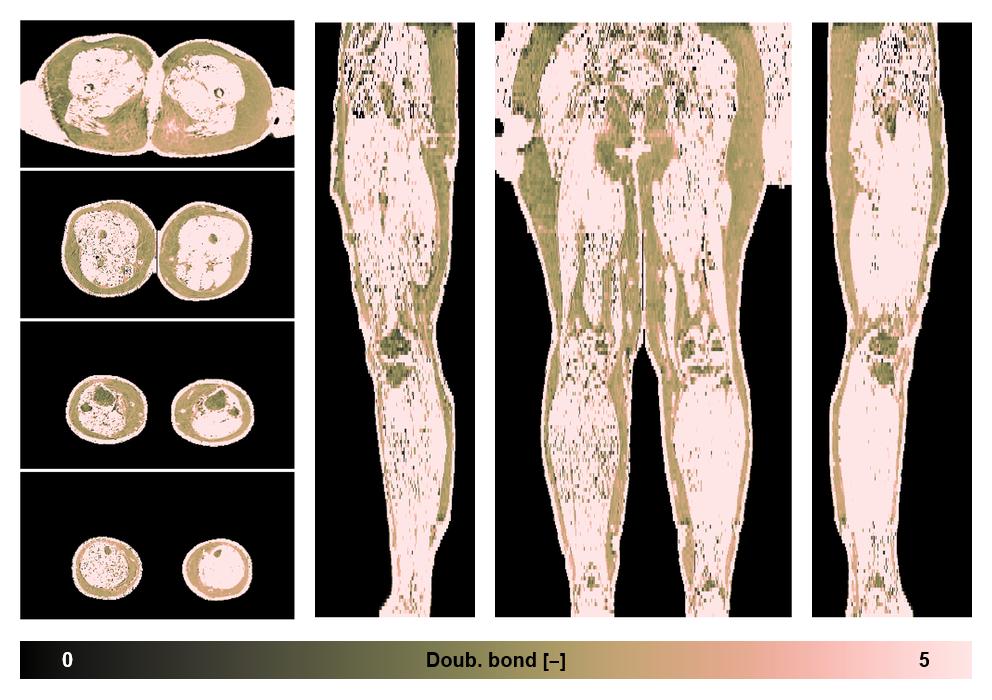

• Number of double bonds in subcutanious fat

Number of double bonds in subcutanious fat.